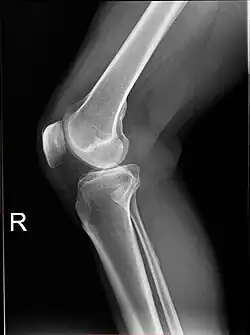

Projectional radiography is the practice of producing two-dimensional images using X-ray radiation. Bones contain a high concentration of calcium, which, due to its relatively high atomic number, absorbs X-rays efficiently. This reduces the amount of X-rays reaching the detector in the shadow of the bones, making them clearly visible on the radiograph. The lungs and trapped gas also show up clearly because of lower absorption compared to tissue, while differences between tissue types are harder to see.[115]

Projectional radiographs are useful in the detection of pathology of the skeletal system as well as for detecting some disease processes in soft tissue. Some notable examples are the very common chest X-ray, which can be used to identify lung diseases such as pneumonia, lung cancer, or pulmonary edema, and the abdominal x-ray, which can detect bowel (or intestinal) obstruction, free air (from visceral perforations), and free fluid (in ascites). X-rays may also be used to detect pathology such as gallstones (which are rarely radiopaque) or kidney stones which are often (but not always) visible. Traditional plain X-rays are less useful in the imaging of soft tissues such as the brain or muscle. One area where projectional radiographs are used extensively is in evaluating how an orthopedic implant, such as a knee, hip or shoulder replacement, is situated in the body with respect to the surrounding bone. This can be assessed in two dimensions from plain radiographs, or it can be assessed in three dimensions if a technique called '2D to 3D registration' is used. This technique purportedly negates projection errors associated with evaluating implant position from plain radiographs.[116]